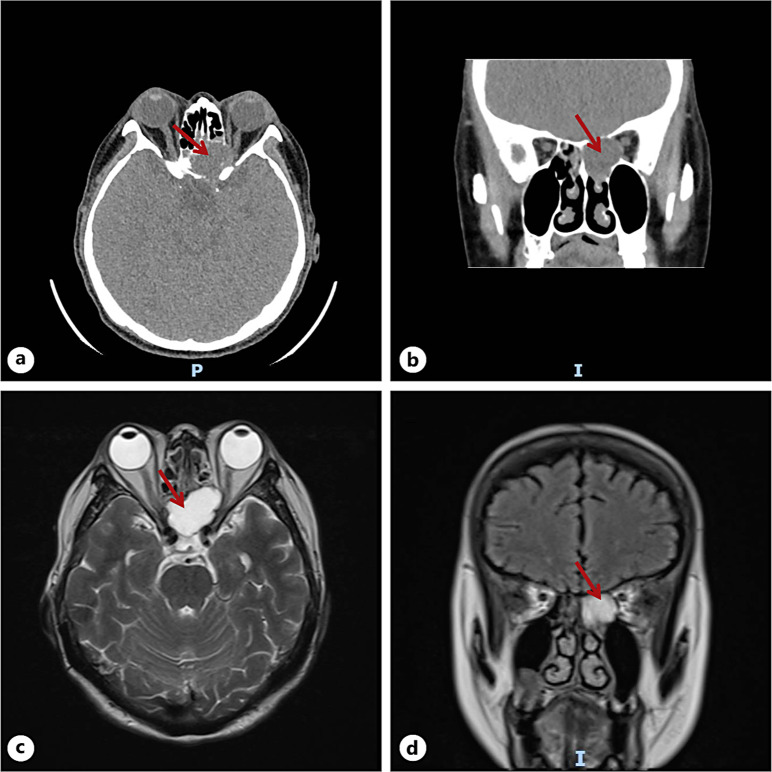

Introduction: Mucoceles are benign, slow-growing cystic formations located within the paranasal sinuses, caused by complete ostial obstruction and accumulation of mucous secretions. Here, we report a case of a patient who initially presented with unilateral painless visual impairment and was ultimately diagnosed with bilateral sphenoid sinus mucoceles (SSMs) after two hospitalizations.

Case presentation: A 67-year-old woman presented with a 7-day history of decreased vision in her left eye. She denied any orbital pain, headache, or restricted eye movement and was diagnosed with retrobulbar ischemic optic neuropathy on the first admission. After drug treatment, the visual acuity of patient improved significantly, but 3 months after discharge, the patient was hospitalized again due to recurrent vision loss accompanied by left orbital pain and left temporal pulsatile headaches. After multiple imaging examinations, the patient was ultimately diagnosed with SSMs and her visual acuity was restored after surgical treatment.